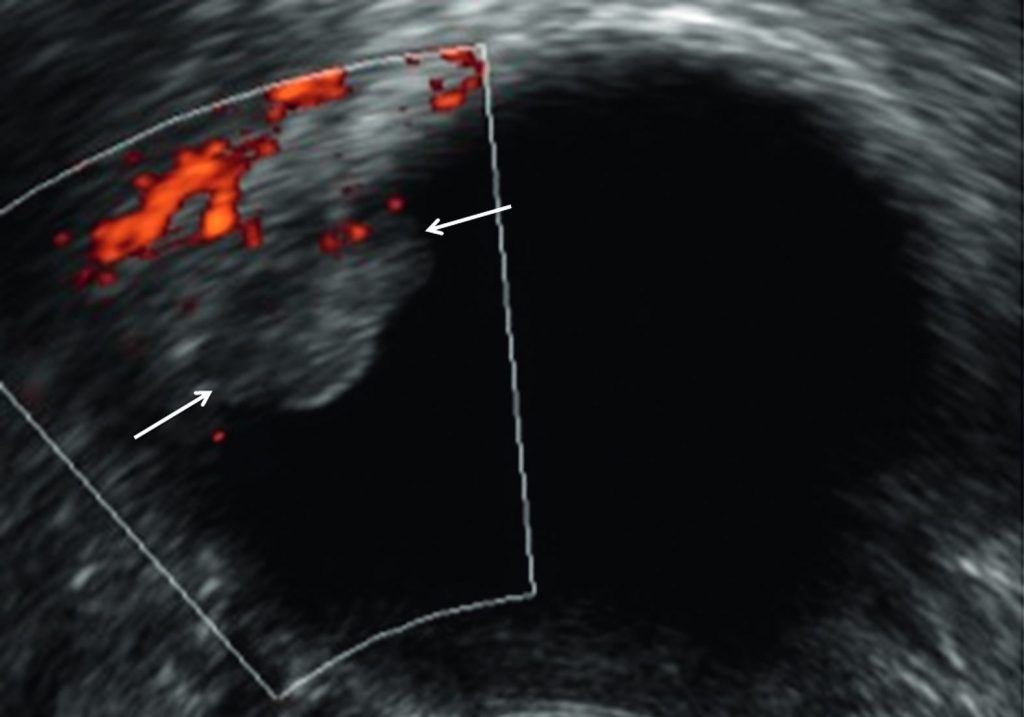

Fig. 23.4 Cystadénome séreux bénin.

Échographie endovaginale en coupe transversale retrouvant un kyste uniloculaire anéchogène contenant une végétation avasculaire en doppler énergie (flèches).

Source : CERF, CNEBMN, 2022.